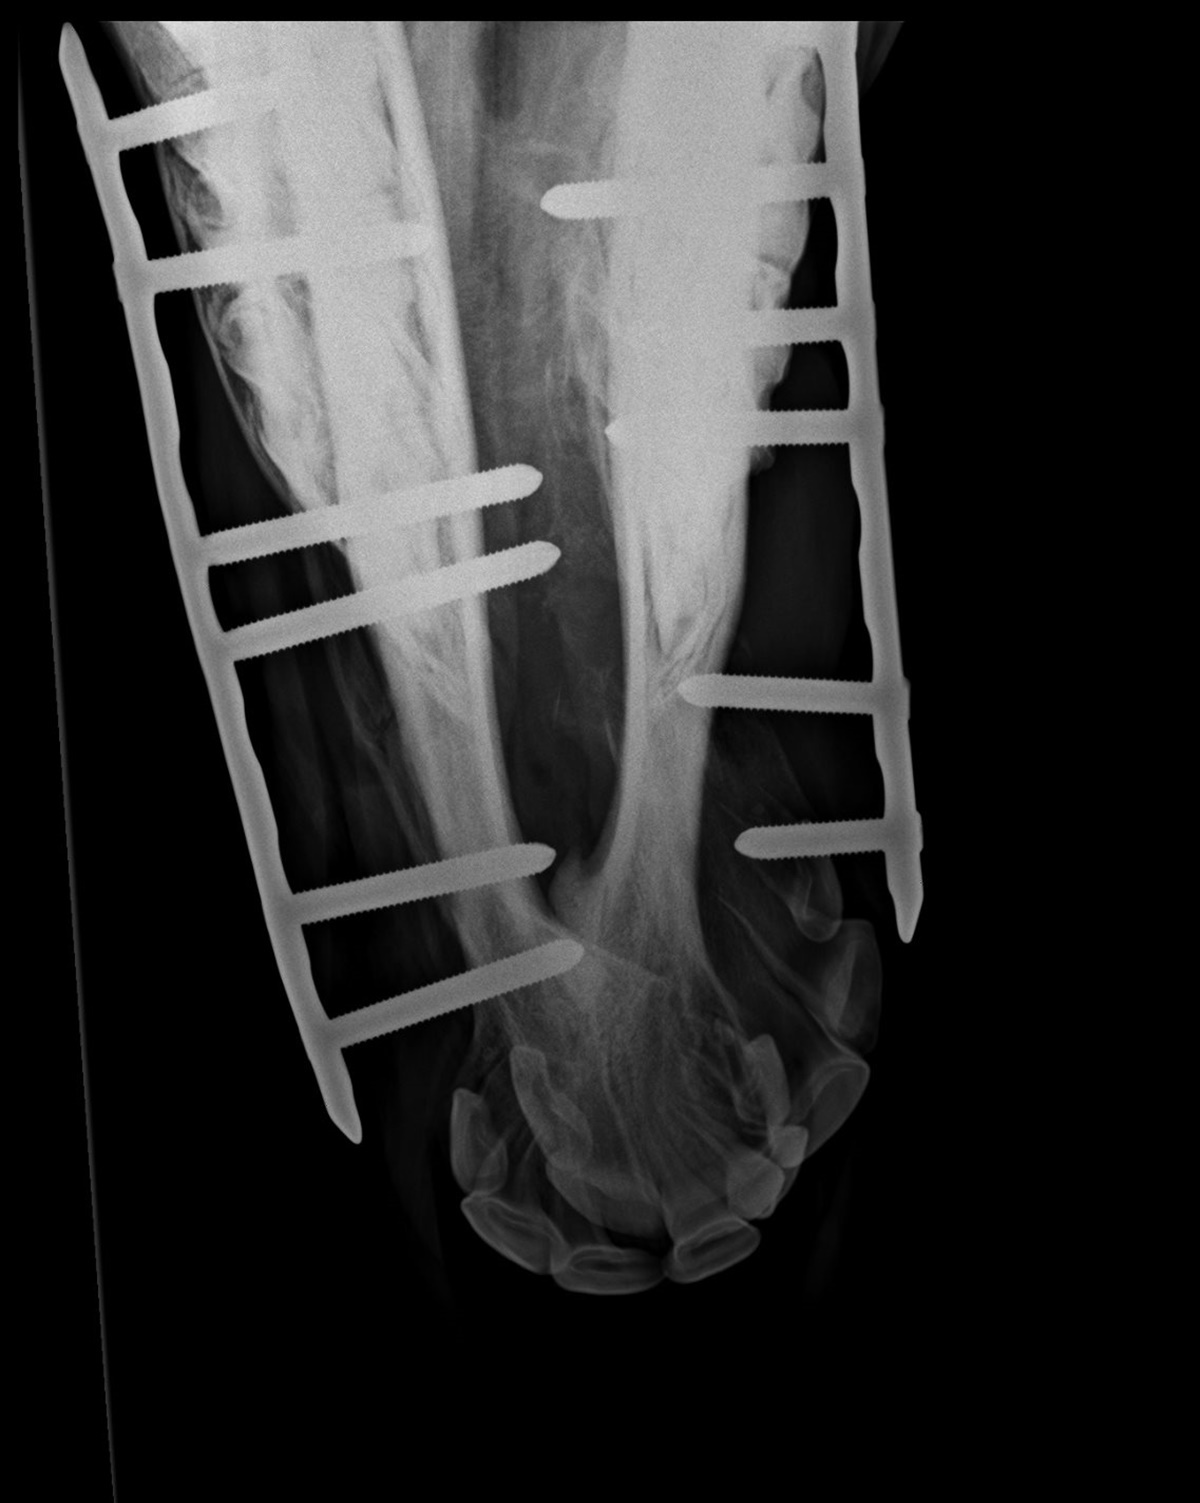

Christina ved ikke præcis hvad dyrlægerne har gjort, men Viljas mule er blevet rettet op, og hun står pt. med skinner og skruer, som skal holde det hele på plads.

– Hun både spiser og drikker fint, og virker ved godt mod. I mandags tog de kontrolrøngten af hende, og hun er ikke særlig hævet efter operationen. Hun virker heller ikke irriteret af skinnerne som sidder på siden af kæberne. Dyrlægen er godt tilfreds med operationen og måden hun takler det hele på, slutter Christina, som desuden fortæller, at Vilja skal blive hos hende.